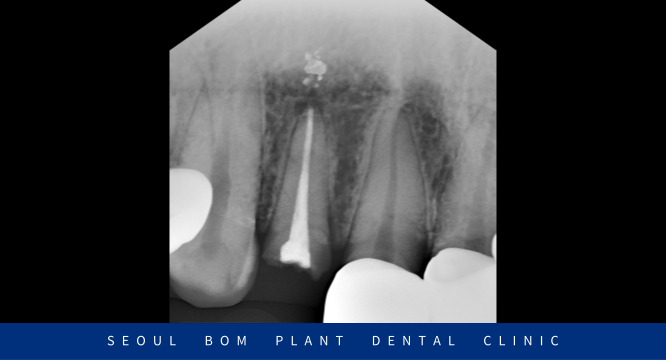

먼저 구강 내를 살펴보았는데요.

위턱 오른쪽 두 번째 앞니(#12)의

치아머리가 기존 보철물과 함께

잇몸 라인까지 다 부러져 나가

잇몸 위 치질 부분이 약 1~2mm 정도

남아있는 상태였습니다.

기존 보철물 안으로 2차 충치가 생기면서

약해진 치질이 강한 저작력을 버티다가

결국 파절 된 상황이었습니다.

환자분과 같이 치질이

얼마 남아 있지 않은 경우에는 치아 뿌리에

Post라는 기둥을 심어 Core로

치아머리 부분을 보강해 주는

Post core를 진행하여 구조를

보강해 주는 것이 예후에 좋습니다.

Post core를 진행한 뒤 치아를 일부 다듬은 후

인상채득을 시행하였으며,